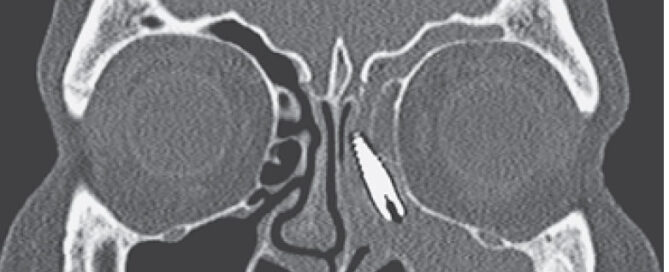

Imagine entrar no dentista para colocar um implante e descobrir [...]

As doenças conhecidas por atrofia de maxila e atrofia de [...]